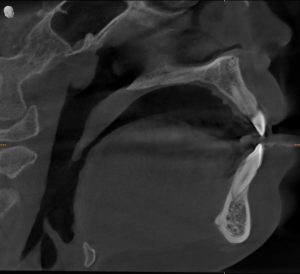

Through clinical examination and radiographic evaluation, we confirmed:

It wasn’t a structural problem — it was habitual mouth breathing.

- Agasthya’s Progress:

His nasal breathing normalized, facial muscle tone improved, and his teeth grinding reduced significantly. He didn’t need further expansion. - Abhaya’s Response:

While breathing improved, she still had a narrow palate and limited airway volume — so we proceeded with palatal expansion to support her growth and bite alignment.